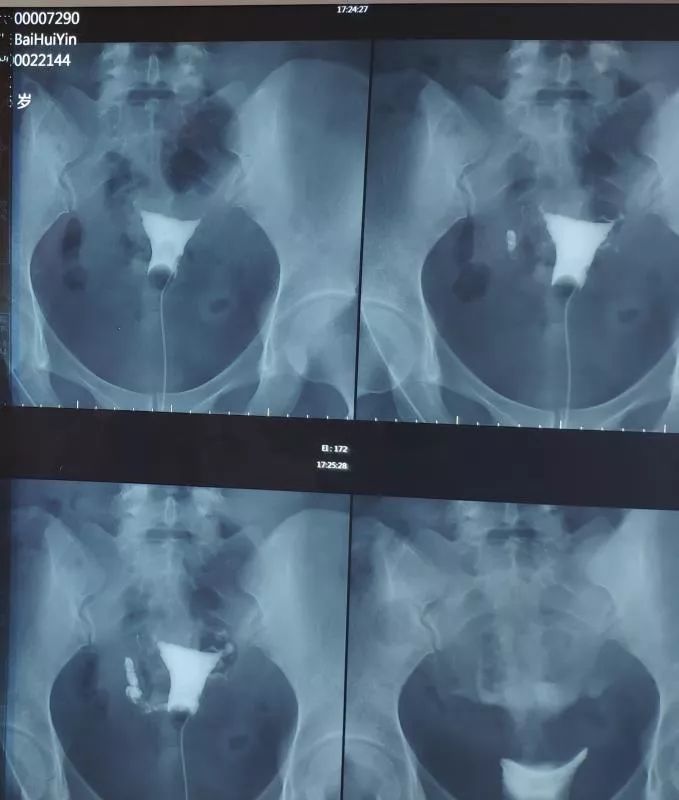

白女士,3月前因不孕症查子宫输卵管造影:输卵管双侧梗阻,少量造影剂弥散(即双侧输卵管不通)如下图: